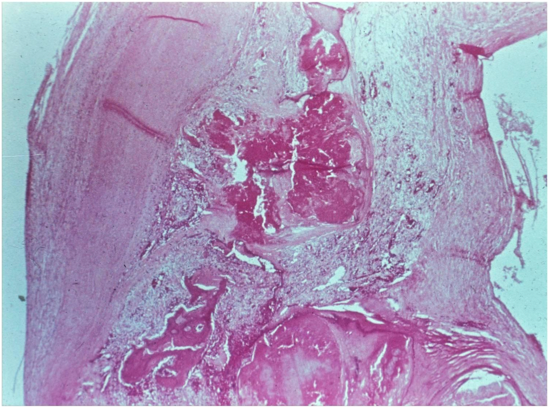

What is shown here?

aortic valve that is calcificed

valvular heart disease

mechanism: Valves have “osteoblast like cells” that cause the deposition of calcium. Ca++ is made inside the fibroelastic tissue of the valve.